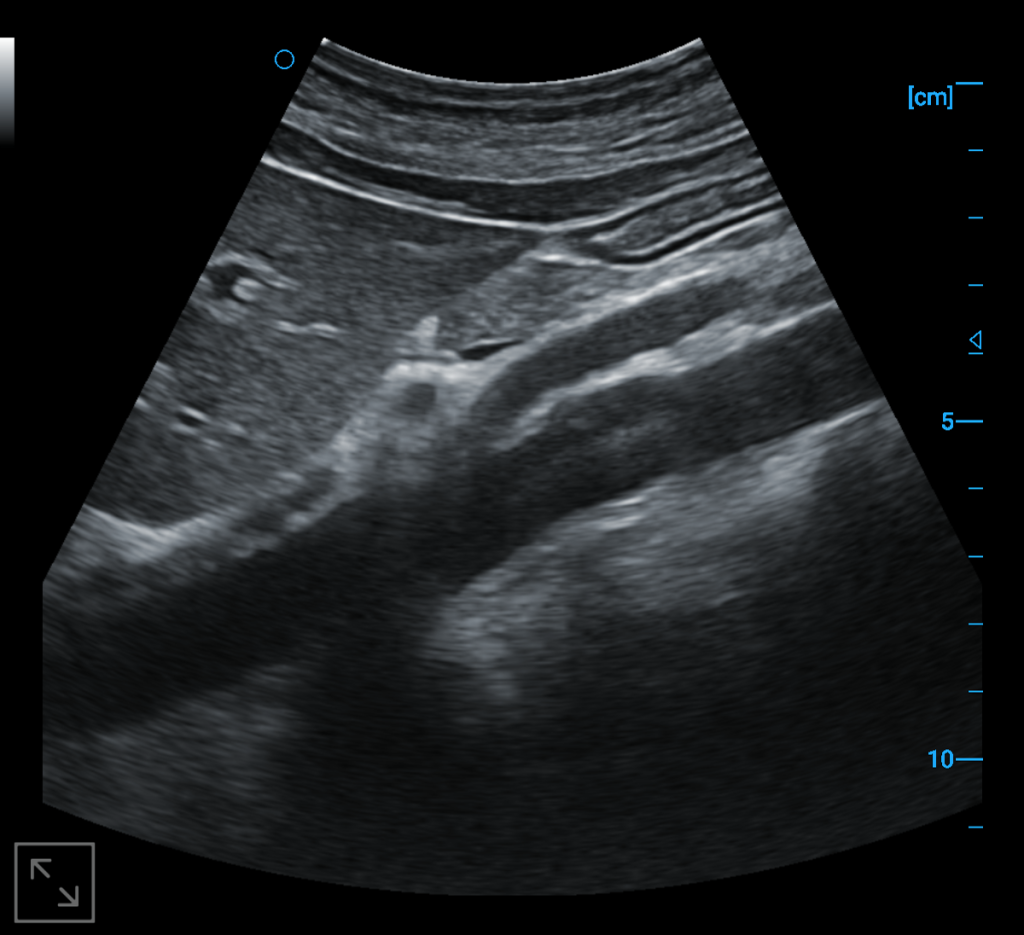

Abdominal aorta B image